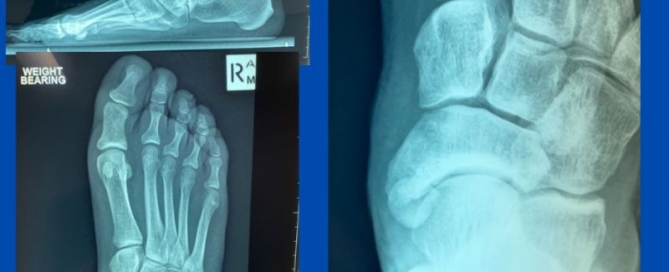

Adult-acquired flat foot (PTTD)

Blog's main page This is a patient who presented with a severely debilitating right flat foot. This has been progressing for approximately two years; however, three months ago, the pain [...]